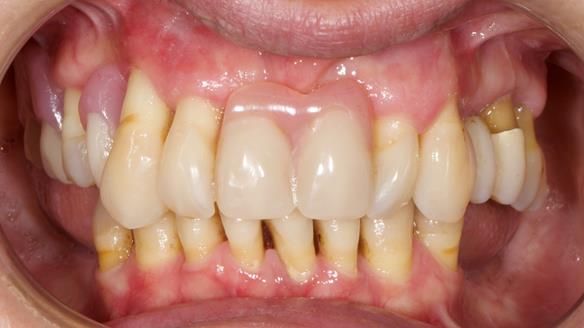

She had previously suffered from generalised periodontitis – stage IV, grade C, currently stable, with reduced attachment across the upper arch.

By the time she came to me, her periodontal condition was stable — but the aesthetics in the upper jaw were very poor.

We provided her with an immediate upper denture (Mk 1), followed by a definitive metal-based upper denture (Mk 2). A lower removable partial denture was discussed, to be made only if needed once the upper treatment was complete. However, at review, this wasn’t necessary — Adnana had excellent neuromuscular control and function, even with a shortened dental arch (SDA).

- A restored smile, restored lip support, and a patient who owned the journey